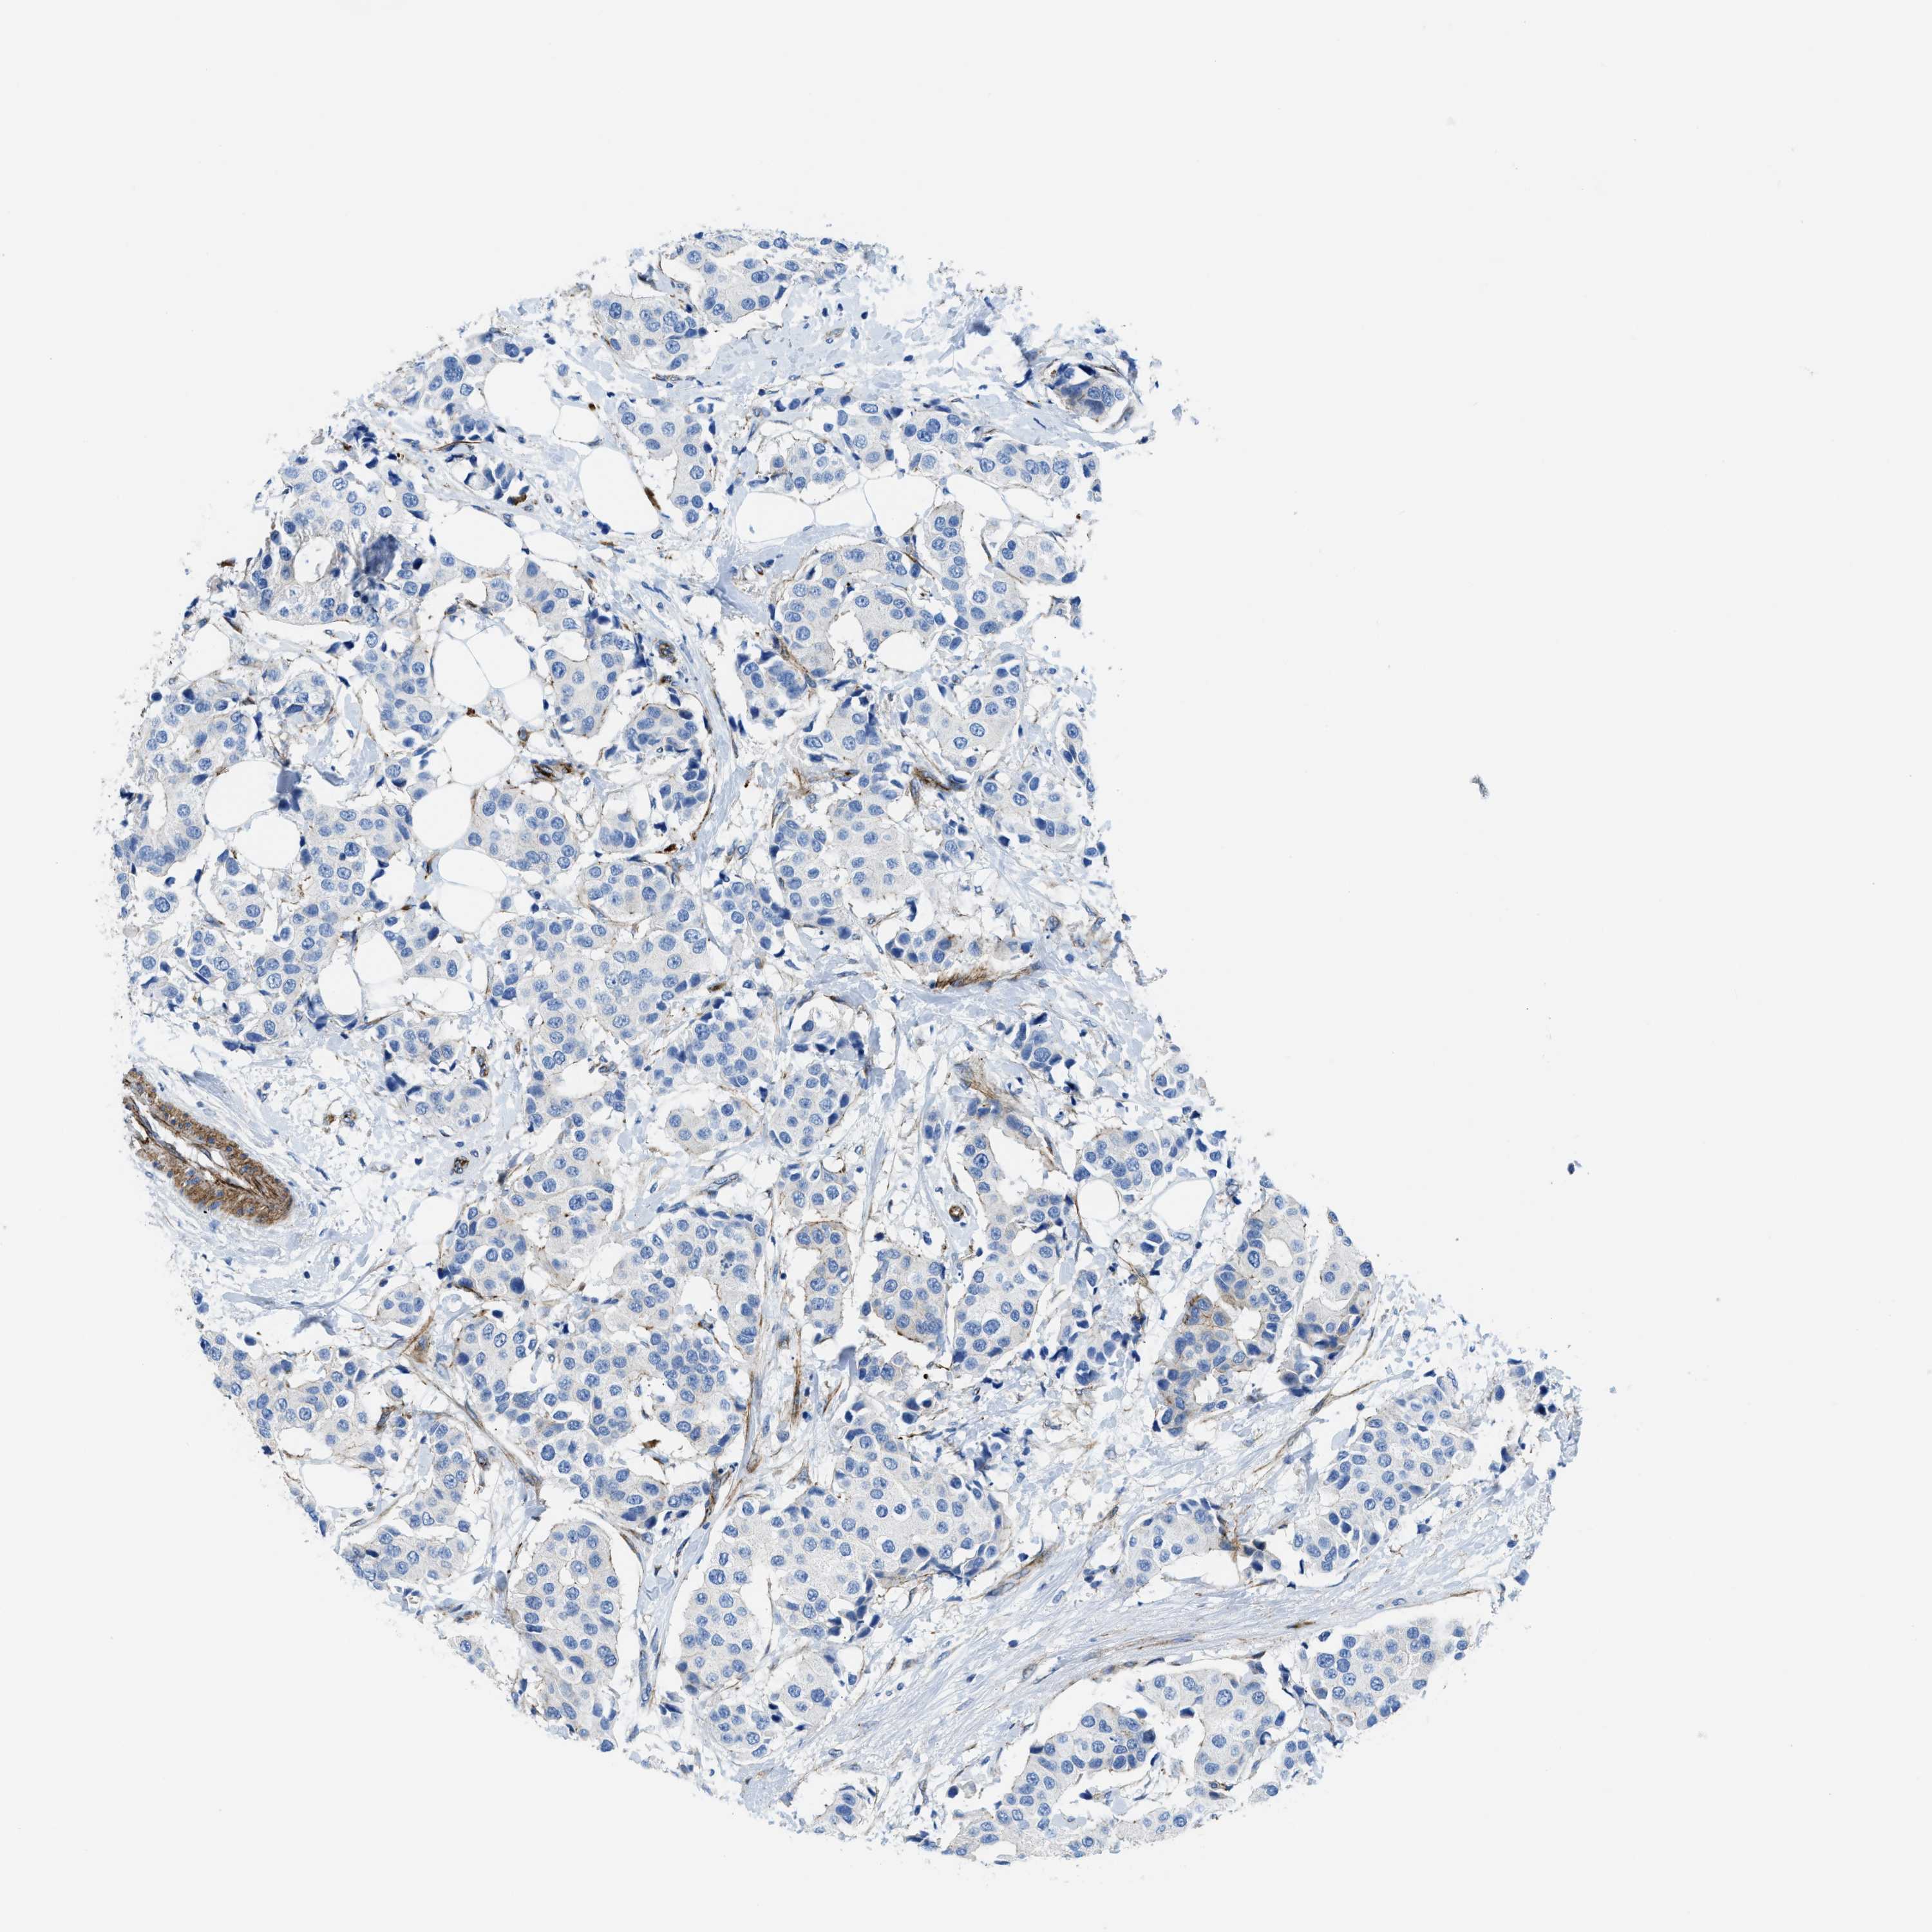

BRCA TCGA BRCA VALIDATION PROTEIN EXPRESSION

ANTIBODIES

AND

VALIDATION